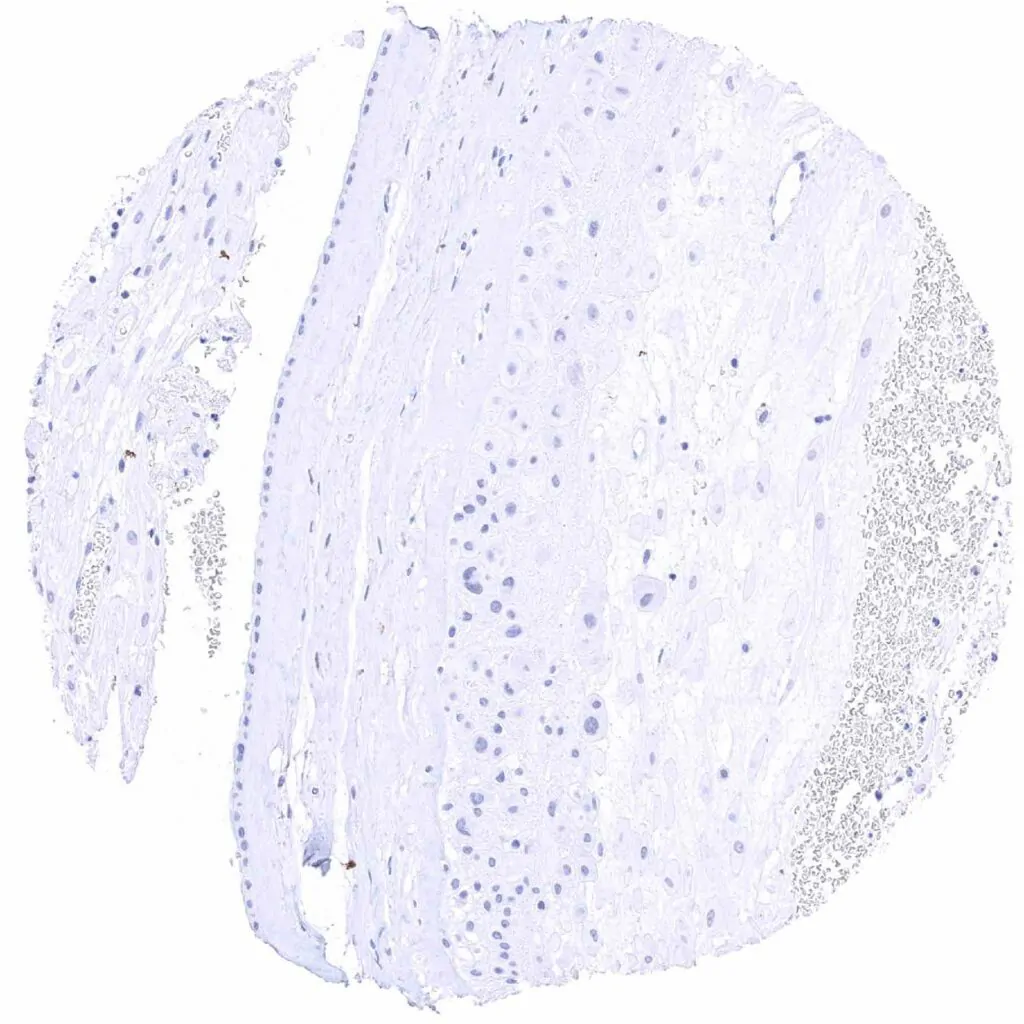

Cerebrum, white matter